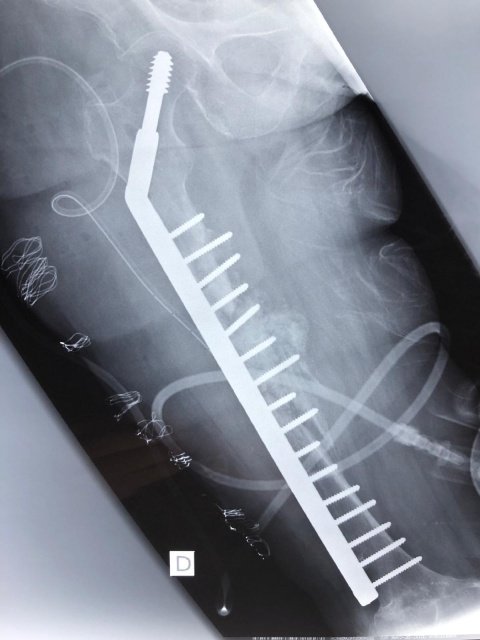

Die Fortbewegung war nur krabbelnd und hüpfend möglich. Im Röntgenbild sah man Residuen der Tibiakopffraktur sowie eine Verkalkung im Bereich der dorsalen Kapsel. Es erfolgte eine Arthrolyse des Kniegelenkes ventral und dorsal, gefolgt von einer redressierenden Gipsanlage (Abb. 4), wodurch die Beugekontraktur auf eine ROM von 0 – 20 – 110° erweitert werden konnte. Die verkürzte Muskulatur wird jetzt physiotherapeutisch behandelt und der Patient war zum Abschluss der Behandlung gehfähig. Ein zweiter wesentlicher Part der chirurgischen Tätigkeit stellte die Revision unzureichender Heilungsergebnisse dar. Die Ursachen hierfür waren heterogen. Fehlende Verfügbarkeit geeigneten Materials und unzureichende Nachbehandlung standen hierbei im Vordergrund. So auch bei unserem 2. Fallbeispiel, einer 51-jährigen Dame, die vor einem Jahr eine Oberschenkelfraktur erlitten hatte und mittels Nagelosteosynthese versorgt wurde. Dieser wanderte proximal aus und bei bestehender Pseudarthrose erfolgte eine Plattenosteosynthese. Leider wurde zur postoperativen Immobilisation eine Mecron-Schiene in Kombination mit einem Rollstuhl gewählt, bei dem leider keine Abstützung des Beines möglich war. So hebelte die Schiene direkt am Ende der Platte und es kam zu einer Anschlussfraktur (Abb. 5) oberhalb der Platte. Diese wurde durch uns revidiert und mit einer DHS mit 16 Löchern ersetzt (Abb. 6). Hierunter konnte letzten Endes eine ausreichende Stabilisierung erreicht werden.